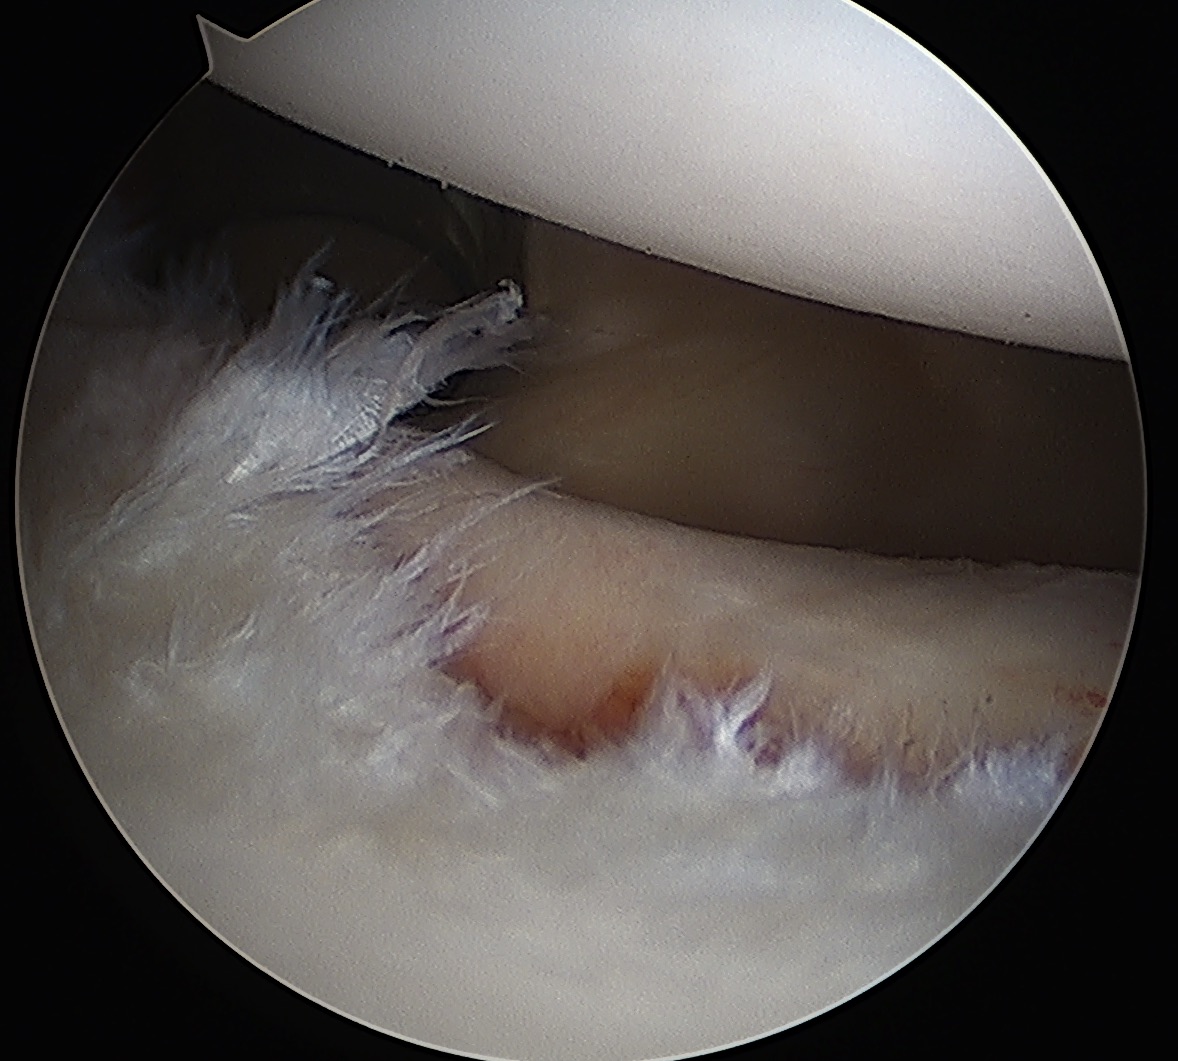

Labrum

Anterior inferior labral tears |

SLAP tears | Posterior labral tears |

Below equator 3 - 6 o'clock |

Mobilize anterior labrum

Mobilize labrum

Labral mobiliser / rasp

- labral tear can be obvious, but may have partially healed or healed medially

- change camera to anterosuperior portal for better view

- mobilize until can see subscapularis muscle underneath

- need to be able to advance labrum medially and superiorly for repair